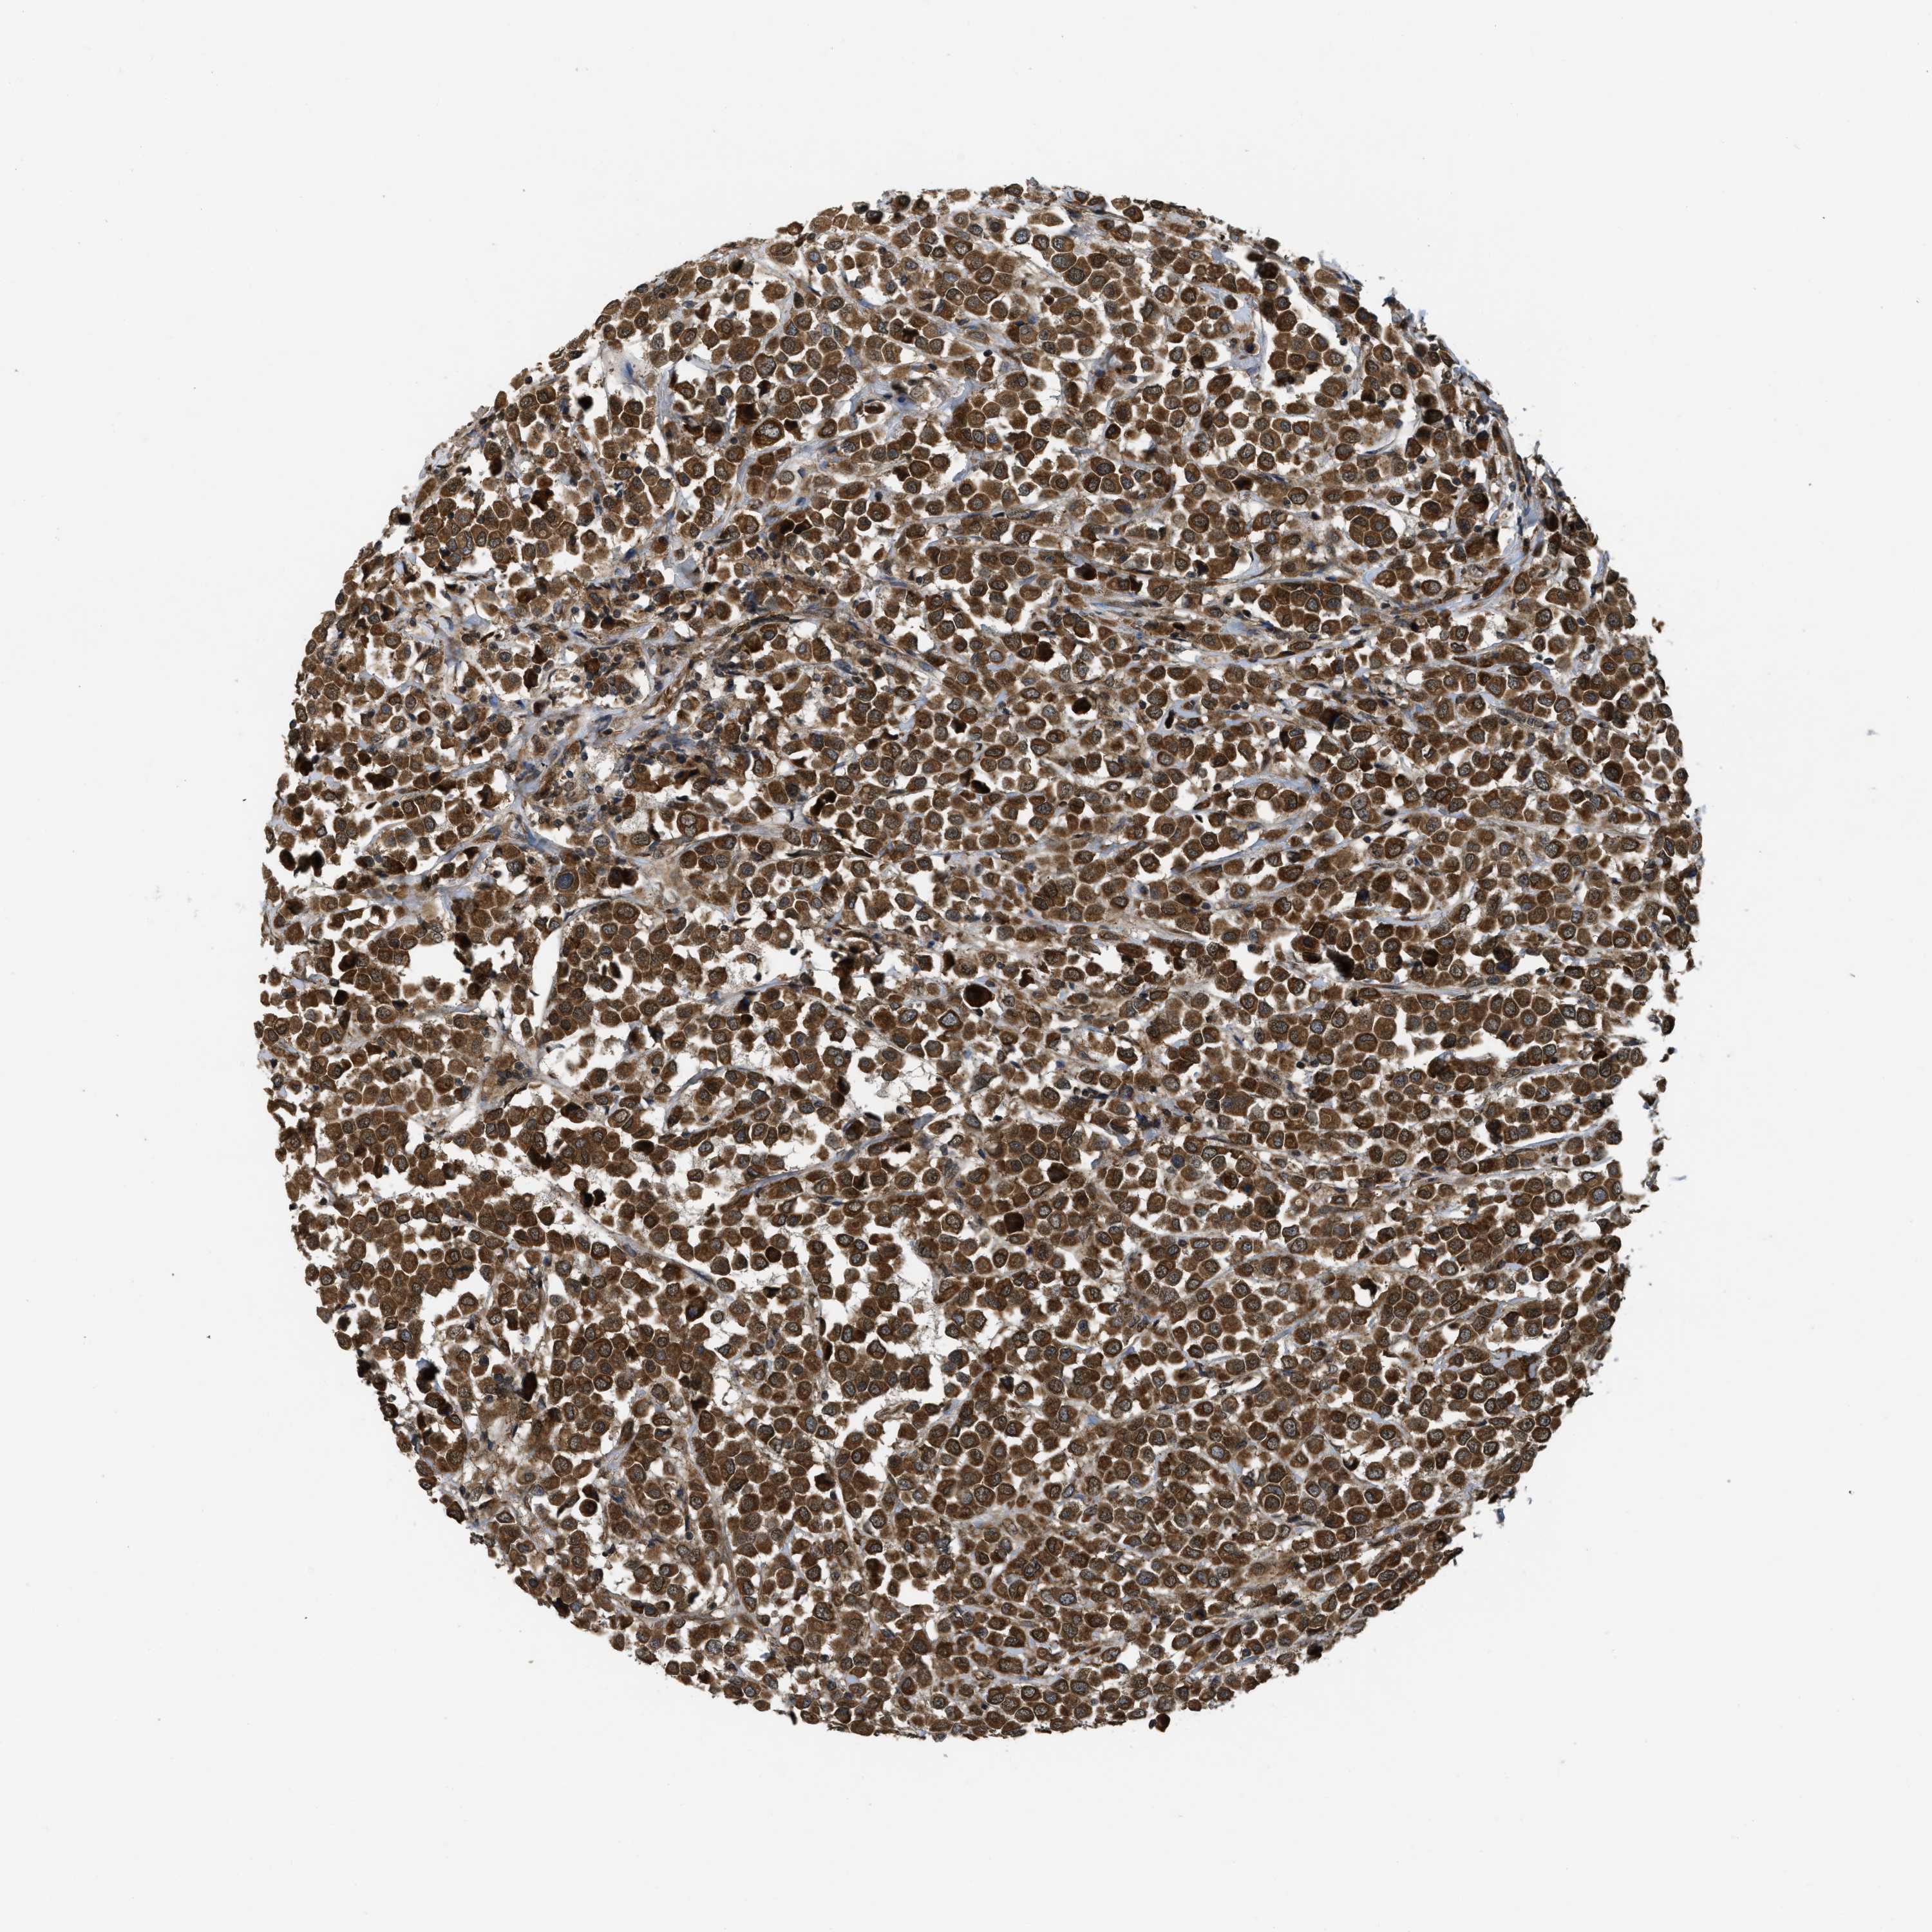

CANCER BREAST CANCER Show tissue menu

Breast cancer

Human cancer